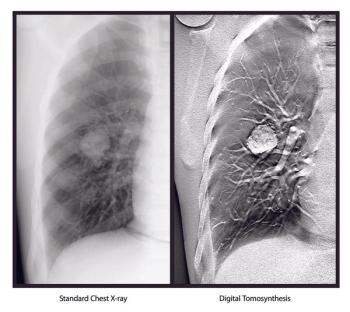

FDA clearance extends digital tomosynthesis to Carestream customers.